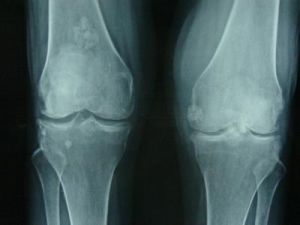

二、影像學診斷

緻密骨瘤顯示隆起,外比光滑,顱骨骨瘤基底寬廣,呈波狀。位內板者則內板增厚。骨密度均勻增加,骨質破壞與骨化程度常不一致。

骨疣常帶蒂,軟骨部可鈣化,呈菜花狀。